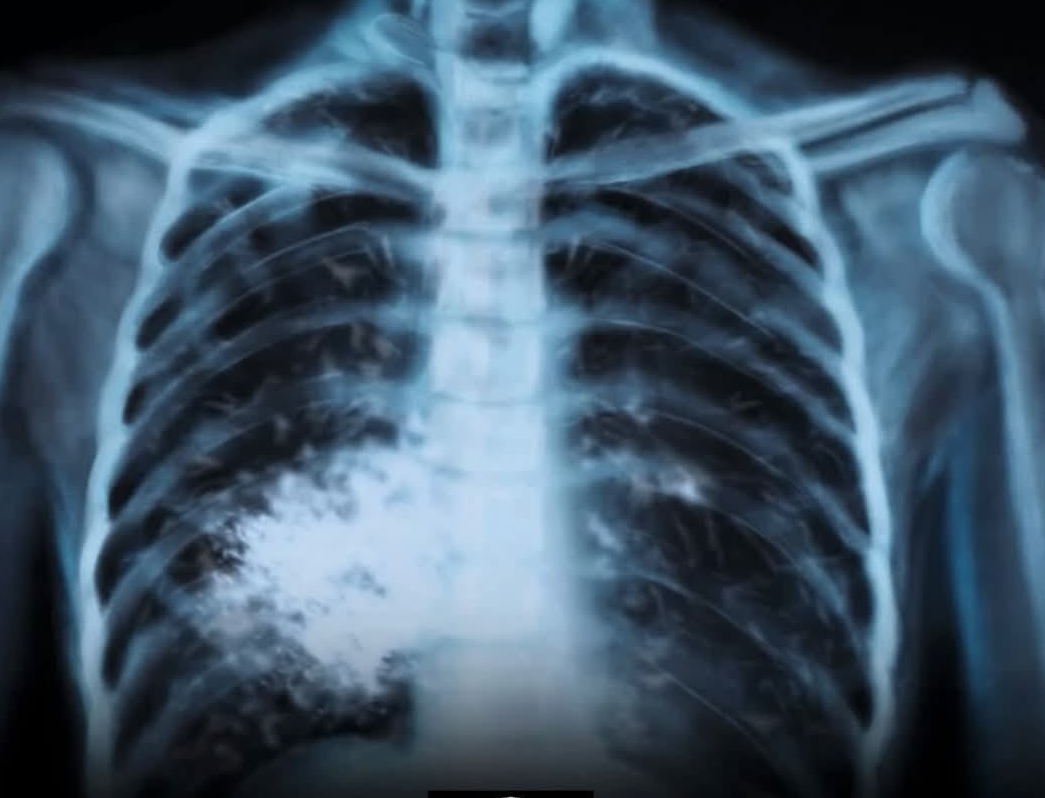

ЦИГАРИТЕ СА ПРОДУКТ, КОЙТО УБИВА ПОЛОВИНАТА ОТ СВОИТЕ ПОТРЕБИТЕЛИ

Ако някога моралът на политици и законотворци в областта на здравеопазването у нас се издигне на национално отговорна висота, а хората разберат, че собственото им здраве зависи от техния личен избор на поведение, тогава може би производителите на тютюневи изделия ще бъдат притиснати в ъгъла и принудени да се откажат от ролята на змията-изкусителка, която изобретява все нови и нови видове тютюневи “ябълки”, с които съблазнява все нови и нови наивници, които вярват, че това е пътя на израстването, знак за независимост и зрялост. Така неусетно желанието им да бъдат забелязани, да бъдат харесани, да станат влиятелни и значими сред тези, с които общуват, ги отвежда не до рая, а до ада на употребяващите никотин. Защото наистина няма значение дали пушиш традиционни или електронни цигари, вейпове, наргилета, бездимни или такива, които си свиваш сам. Един ден собственото ти тяло ще те изправи пред нечий лекарски кабинет.